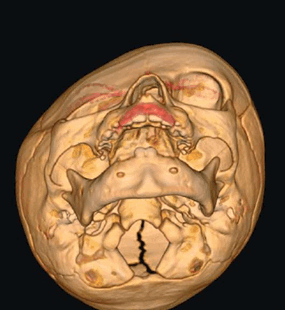

Рис. № 6 Брахиоцефалия

а) - до и после операции

б), в) - СКТ снимки после установки дистракторов.